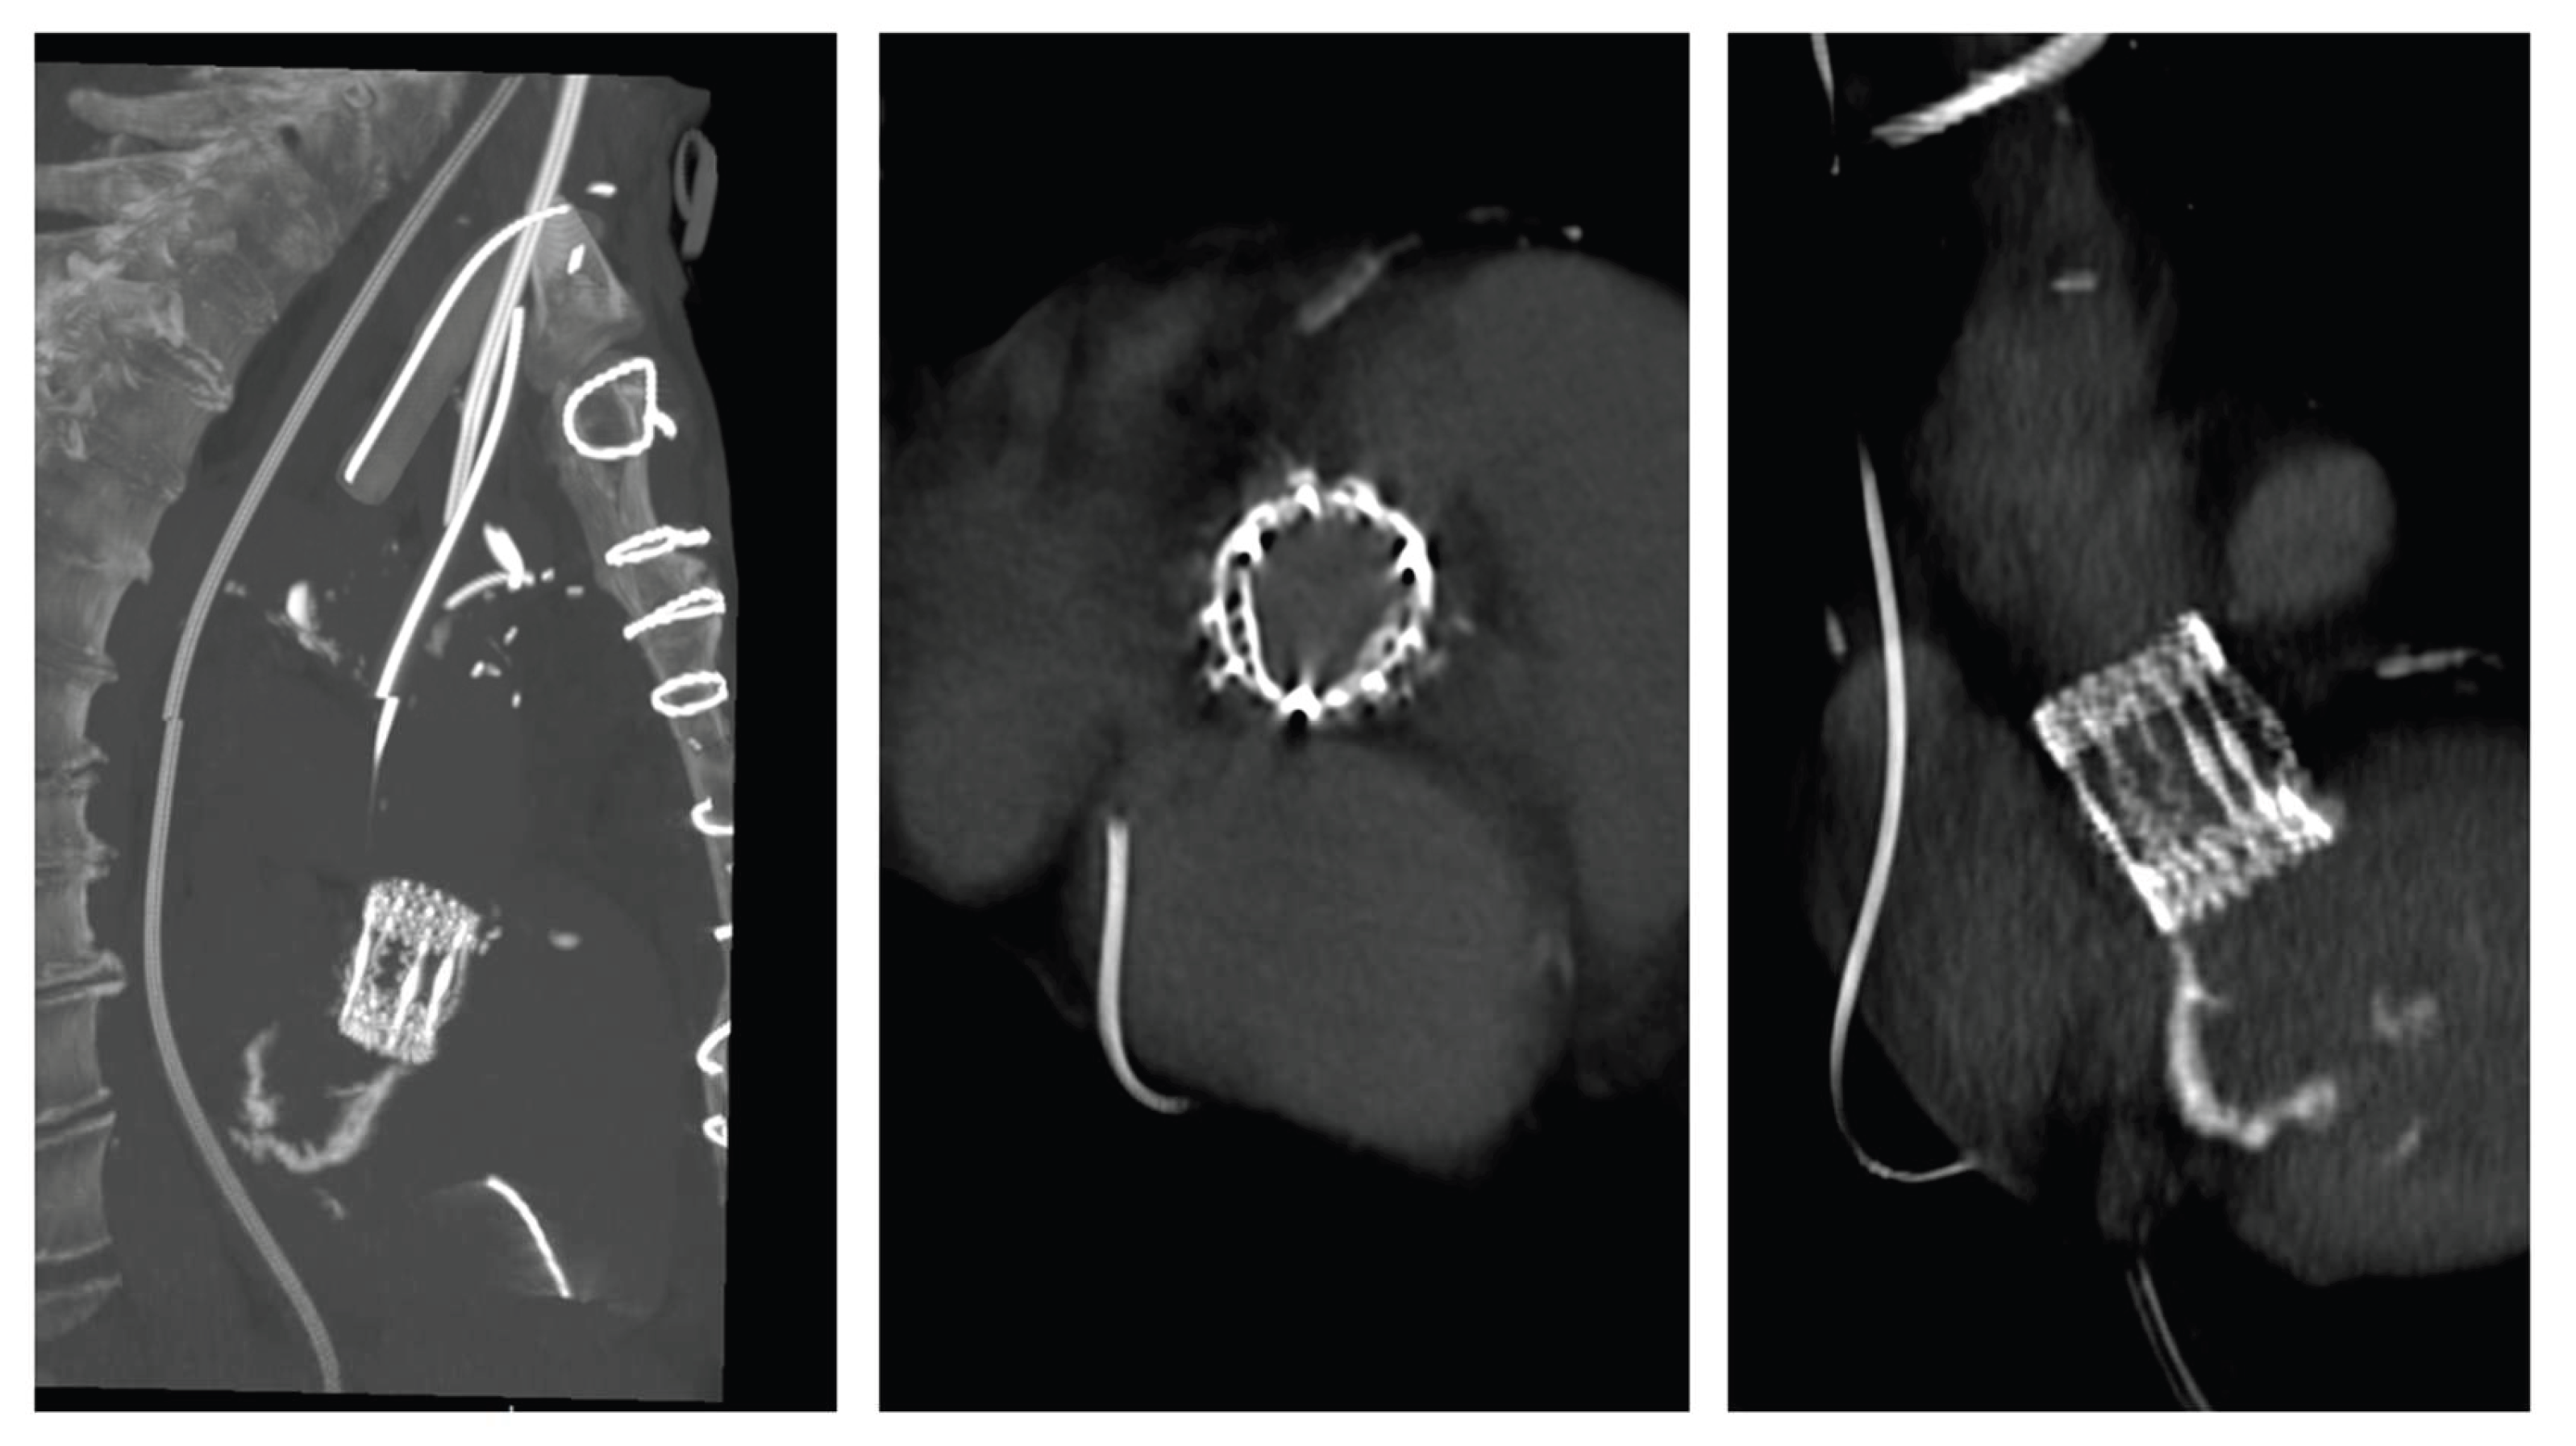

The patient experienced rapid clinical deterioration, progressing to multiorgan failure characterized by septic and cardiogenic shock, acute hepatic dysfunction (shock liver), acute renal failure, septic encephalopathy, disseminated intravascular coagulation, and new-onset atrial flutter. Despite a calculated in-hospital mortality risk of 89.5% based on the EuroSCORE II, the severity of the clinical scenario mandated immediate salvage surgery. A redo median sternotomy was undertaken in a technically complex setting, complicated by the absence of the pericardium and dense mediastinal adhesions from the previous surgery. Careful and meticulous dissection allowed for the safe identification of the great vessels. Central cannulation was achieved via the aortic arch for arterial return and bicaval venous access for drainage. Cardiopulmonary bypass (CPB) was initiated under normothermic conditions, ensuring adequate systemic perfusion. The aorta was cross-clamped, and a transverse aortotomy was performed. Myocardial protection was provided through the administration of cold blood cardioplegia directly into the coronary ostia, with repeated doses to maintain optimal myocardial preservation throughout the procedure. Intraoperative exploration revealed extensive destruction: the left neocuspidal leaflet was completely perforated, and a large, highly mobile vegetation was found on the ventricular aspect of the valve. Furthermore, a sub- annular abscess was identified, extending from the left–right commissure into both the left and right sinuses of Valsalva. Radical debridement of all infected and necrotic tissue was undertaken, with evacuation of purulent material. The abscess cavity was meticulously excised until only macroscopically healthy tissue remained. The resulting defect, involving the annular region and extending approximately one centimeter into both sinuses, was reconstructed using two layers of continuous 4-0 Prolene sutures. Given the fragility of the annular tissue and the extensive debridement required, the use of a conventional sutured bioprosthesis was deemed inadvisable. A medium-sized Perceval sutureless bioprosthetic valve was therefore selected and deployed successfully. The aortotomy was closed using the Blalock technique with two layers of 5-0 Prolene sutures. Weaning from CBP proved challenging due to biventricular dysfunction in the context of preoperative multiorgan failure. As a result, femoro-femoral veno-arterial extracorporeal membrane oxygenation (VA-ECMO) was instituted intraoperatively to provide circulatory support and facilitate end-organ recovery. The total cross-clamp time was 58 minutes whilst CBP time was 125 minutes. Hemodynamic stabilization was gradually achieved, and ECMO was successfully explanted after 5 days. The patient remained in the intensive care unit for three weeks, during which progressive clinical improvement was observed. Transthoracic echocardiography performed prior to ICU discharge demonstrated normal function of the implanted Perceval valve (Figure 2 and Figure 3), with no evidence of paravalvular leakage or residual vegetations. At three-month follow-up, the patient remained clinically stable, and repeat imaging confirmed preserved valve function without signs of recurrent endocarditis.

Figure 3. Three-dimensional CT reconstruction demonstrating the Perceval sutureless valve in optimal position.